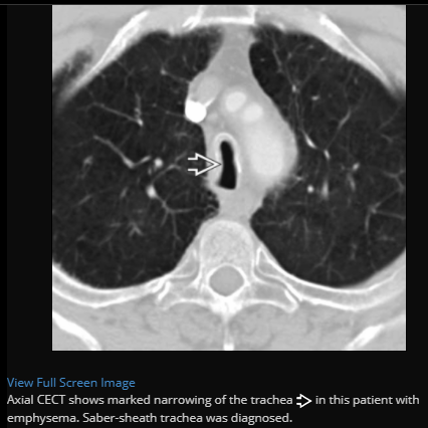

Saber sheath trachea, pathognomonic for COPD

Best diagnostic clue: Side-to-side narrowing of intrathoracic trachea